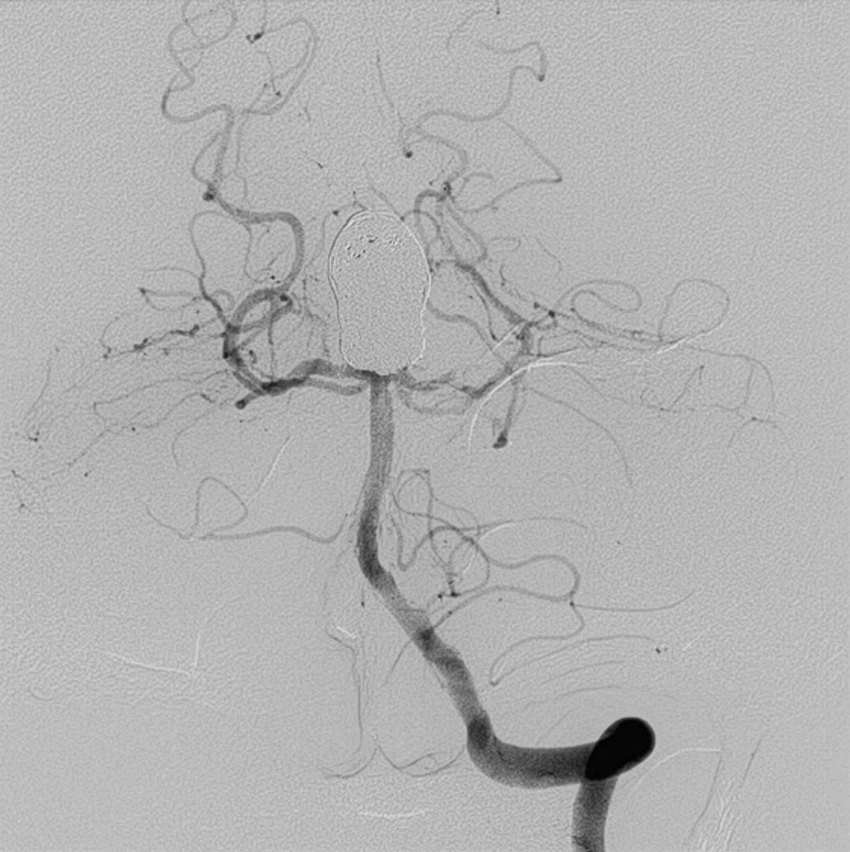

1) 혈관내 치료(Endovascular Treatment): 두개골을 열지 않고 바로 동맥 혈관 내부로 카테타를 넣고, 미세 카테타를 뇌동맥류로 삽입한 후 백금실(코일)을 충전하는 치료 방법이다. 코일 색전술로 알려져 있으며, 파열 뇌동맥류, 즉 지주막하 출혈의 경우 첫 번째로 선택되는 치료방법이다.

기저동맥 첨부 뇌동맥류

기저동맥 첨부 뇌동맥류 코일색전 후